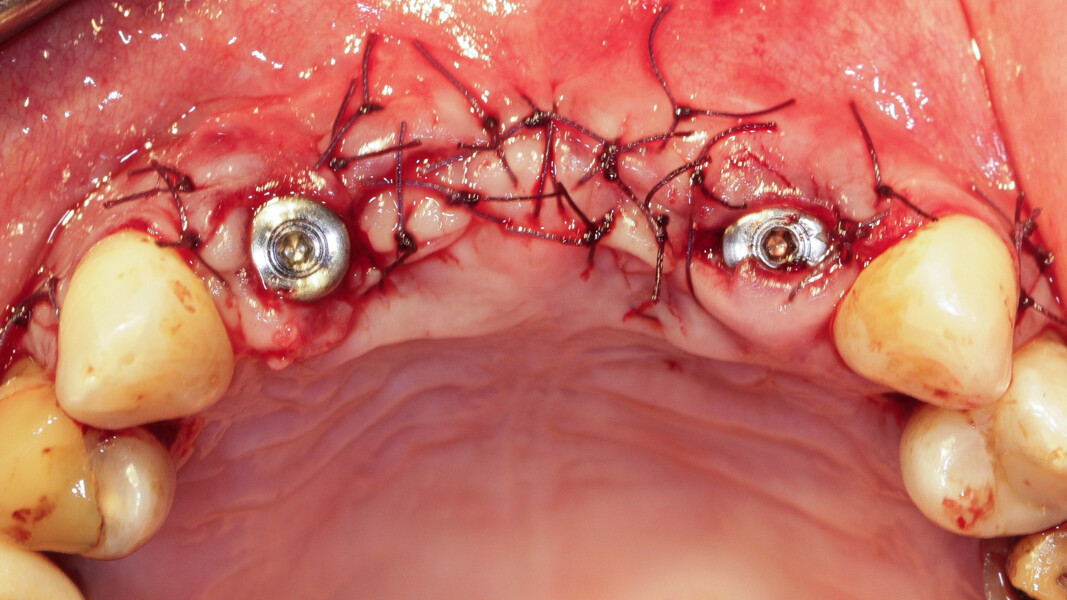

À l’examen, on observe une mobilité des quatre incisives maxillaires, une insuffisance osseuse verticale et horizontale, associées notamment au niveau de 11 et 21, la présence de plaque, de tartre et d’inflammation gingivale, surtout au niveau du bloc antérieur maxillaire. On note également la présence d’une dent de sagesse (dent 18) perdue (Figs. 24–26).

Nous réalisons un lambeau avec une incision crestale décalée en palatin en 11 et 21, sulculaire en 12, 13, 22, 23, en prenant soin de préserver les papilles interdentaires, ainsi que deux décharges verticales en distal des canines. Nous réalisons un décollement de pleine épaisseur (Figs. 28 et 29). Les dents (12, 22 et 18) sont facilement extraites et les alvéoles curetées avec soins. Deux implants (4*13) sont positionnés dans la paroi palatine des alvéoles, il subsiste une déhiscence vestibulaire en 22. Les racines de 12, 22 et 18 sont séparées dans le sens de la longueur. Les racines préparées comme indiqué ci-dessus, sont vissées en vestibulaire et en occlusal de la crête, au moyen de vis d’ostéosynthèse (diamètre 0,9 mm), afin de reconstruire la crête osseuse au niveau des inters de bridge ainsi que la paroi vestibulaire de la crête au niveau de 22 (Figs. 30 et 31). Le gap vestibulaire entre les implants et la crête ainsi que l’espace entre la crête et le greffon au niveau de 21, sont comblés avec un matériau d’origine synthétique (Collapat II Symatese). Le lambeau est tracté, suturé coronairement avec un fil tressé synthétique 5.0 (Fig. 32). Des piliers coniques droits pour prothèse plurale transvissée sont posés, et une empreinte prise à la fin de l’intervention (Fig. 33). Un provisoire est réalisé dans la journée par notre laboratoire de prothèse et posé le soir même. (Figs. 34 et 35)